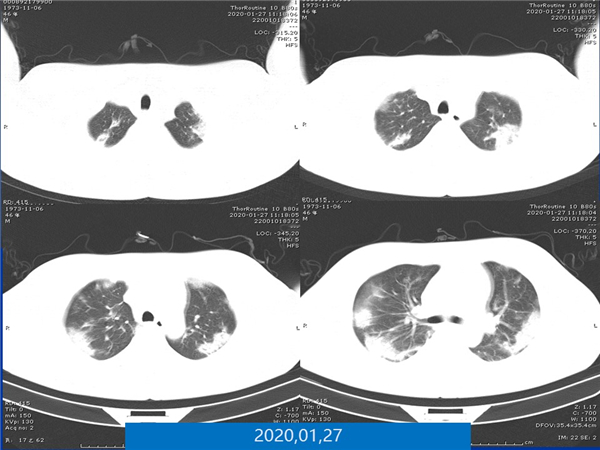

【病例分享】新型冠狀病毒感染肺部CT影像4例(常德市第一人民醫(yī)院)

幻燈片5.jpg